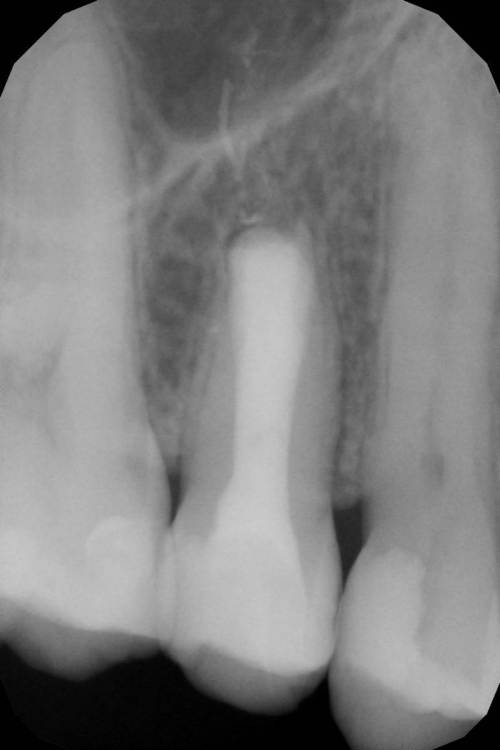

Гарриевич Опубликовано 2 августа, 2018 Автор Поделиться Опубликовано 2 августа, 2018 Вот вся история в картинках 13 Ссылка на комментарий

ger_berra Опубликовано 9 августа, 2018 Поделиться Опубликовано 9 августа, 2018 Вот вся история в картинкахF3CD8F8E-36A2-482B-BFD4-6A0883546283.jpeg2A06B29D-2BDF-4869-A8F8-E02567619146.jpeg47F31C36-F9FE-40C6-9236-3A6203A894B7.jpeg8459AB75-F819-4664-9906-DB4BDCE505D2.jpeg9937DA00-9922-402C-AA29-5DD806AA0714.jpeg37DDB315-6893-49F4-A949-06BC6B58F996.jpegОтличный результат! 1 Ссылка на комментарий